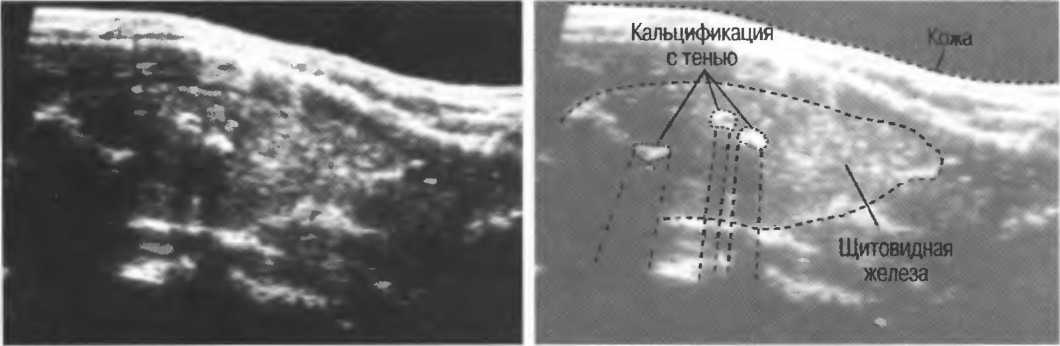

Тени

Кости, камни и кальцинаты дают акустическую тень. Ультразвук не может проходить через кость, если она только не очень тонкая (как, например, кости черепа у новорожденного). При необходимости рассмотреть структуры, расположенные глубже, необходимо использовать различные углы наклона датчика (рис. 17а,б).

Рис. 17а. Большая акустическая тень за камнем в желчном пузыре.